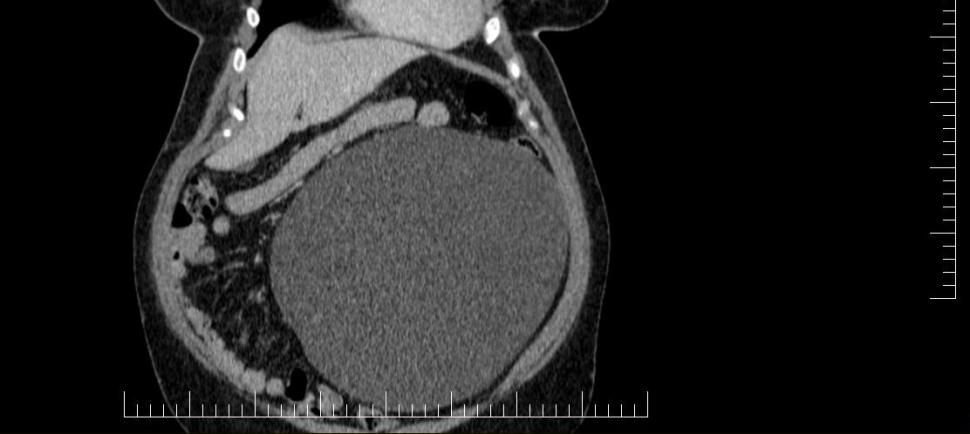

Chist ovarian de 4,5 kilograme, extirpat cu succes de la o pacientă la un spital din Sibiu

Sursa foto: Facebook Spitalul Militar de Urgență „Dr. Alexandru Augustin” Sibiu Foto 1/2